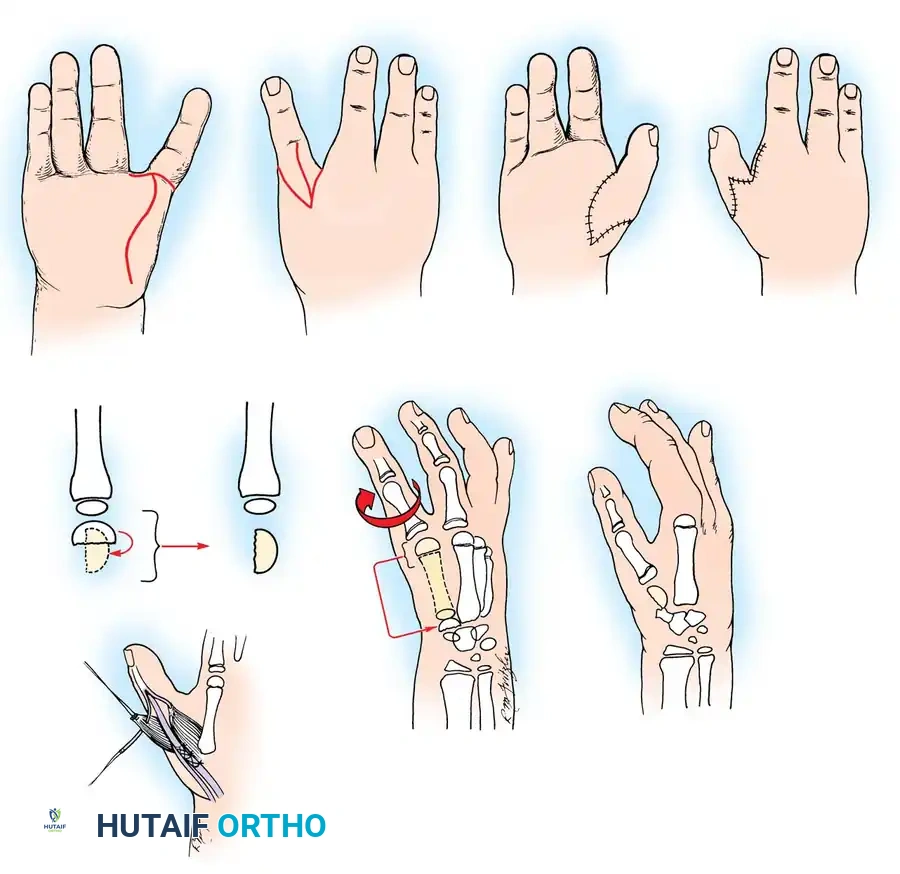

The Krukenberg Operation: Biomechanics and Indications

The Krukenberg procedure converts the forearm into a sensate pincer by separating the radius and ulna into two independent, opposing rays. Its primary advantage over prosthetic rehabilitation is the preservation of tactile sensibility and proprioception. This makes it an exceptionally valuable procedure for bilateral upper extremity amputees, particularly those who are blind, as it allows them to interact with their environment using direct sensory feedback.

🔪 Surgical Technique: The Krukenberg Procedure (Technique 14-14)

- Incision and Flap Design: Make a longitudinal incision on the flexor surface of the forearm, biased slightly toward the radial side. Make a corresponding incision on the dorsal surface, biased toward the ulnar side. On the dorsal surface, elevate a V-shaped flap to form the new web space at the proximal junction of the rays.

- Muscle Separation: Systematically separate the forearm musculature into two distinct functional groups:

- Radial Ray (Adductors/Abductors): Comprises the radial wrist flexors and extensors, the radial half of the flexor digitorum sublimis (FDS), the radial half of the extensor digitorum communis (EDC), the brachioradialis, the palmaris longus, and the pronator teres.

- Ulnar Ray (Adductors/Abductors): Comprises the ulnar wrist flexors and extensors, the ulnar half of the FDS, and the ulnar half of the EDC.

- Debulking: If the muscle mass makes the stump too bulky or precludes tension-free skin closure, resect the pronator quadratus, flexor digitorum profundus (FDP), flexor pollicis longus (FPL), abductor pollicis longus (APL), and extensor pollicis brevis (EPB).

- Crucial Step: Take absolute care not to disturb the pronator teres, as it is the primary motor for the radial ray.

- Interosseous Membrane Division: Incise the interosseous membrane longitudinally along its ulnar attachment. Extreme caution must be exercised to preserve the anterior interosseous artery and nerve.

- Osteotomy and Alignment: The radial and ulnar rays should separate 6 to 12 cm at their tips. Motion occurs proximally at the radiohumeral and proximal radioulnar joints. The opposing distal ends of the rays must touch during active closure; if they do not, perform a corrective osteotomy of the radius or ulna.

- Skin Coverage: Excise excess subcutaneous fat. Rotate the skin around each ray and close it so that the suture lines do not lie on the opposing (contact) surfaces of the pincers. Apply split-thickness skin grafts to any remaining defects, ensuring the tactile contact surfaces are covered by sensate, full-thickness skin.

- Closure and Drainage: Suture the dorsal V-flap into the proximal junction to create the web. Insert small rubber drains, obtain meticulous hemostasis after tourniquet deflation, and apply a bulky compression dressing with the rays separated by at least 6 cm.

Postoperative Protocol: The limb is strictly elevated for 3 to 4 days to minimize edema. Sutures are removed at 14-21 days. Intensive rehabilitation begins at 2 to 3 weeks to train the patient in independent abduction and adduction of the newly formed rays.